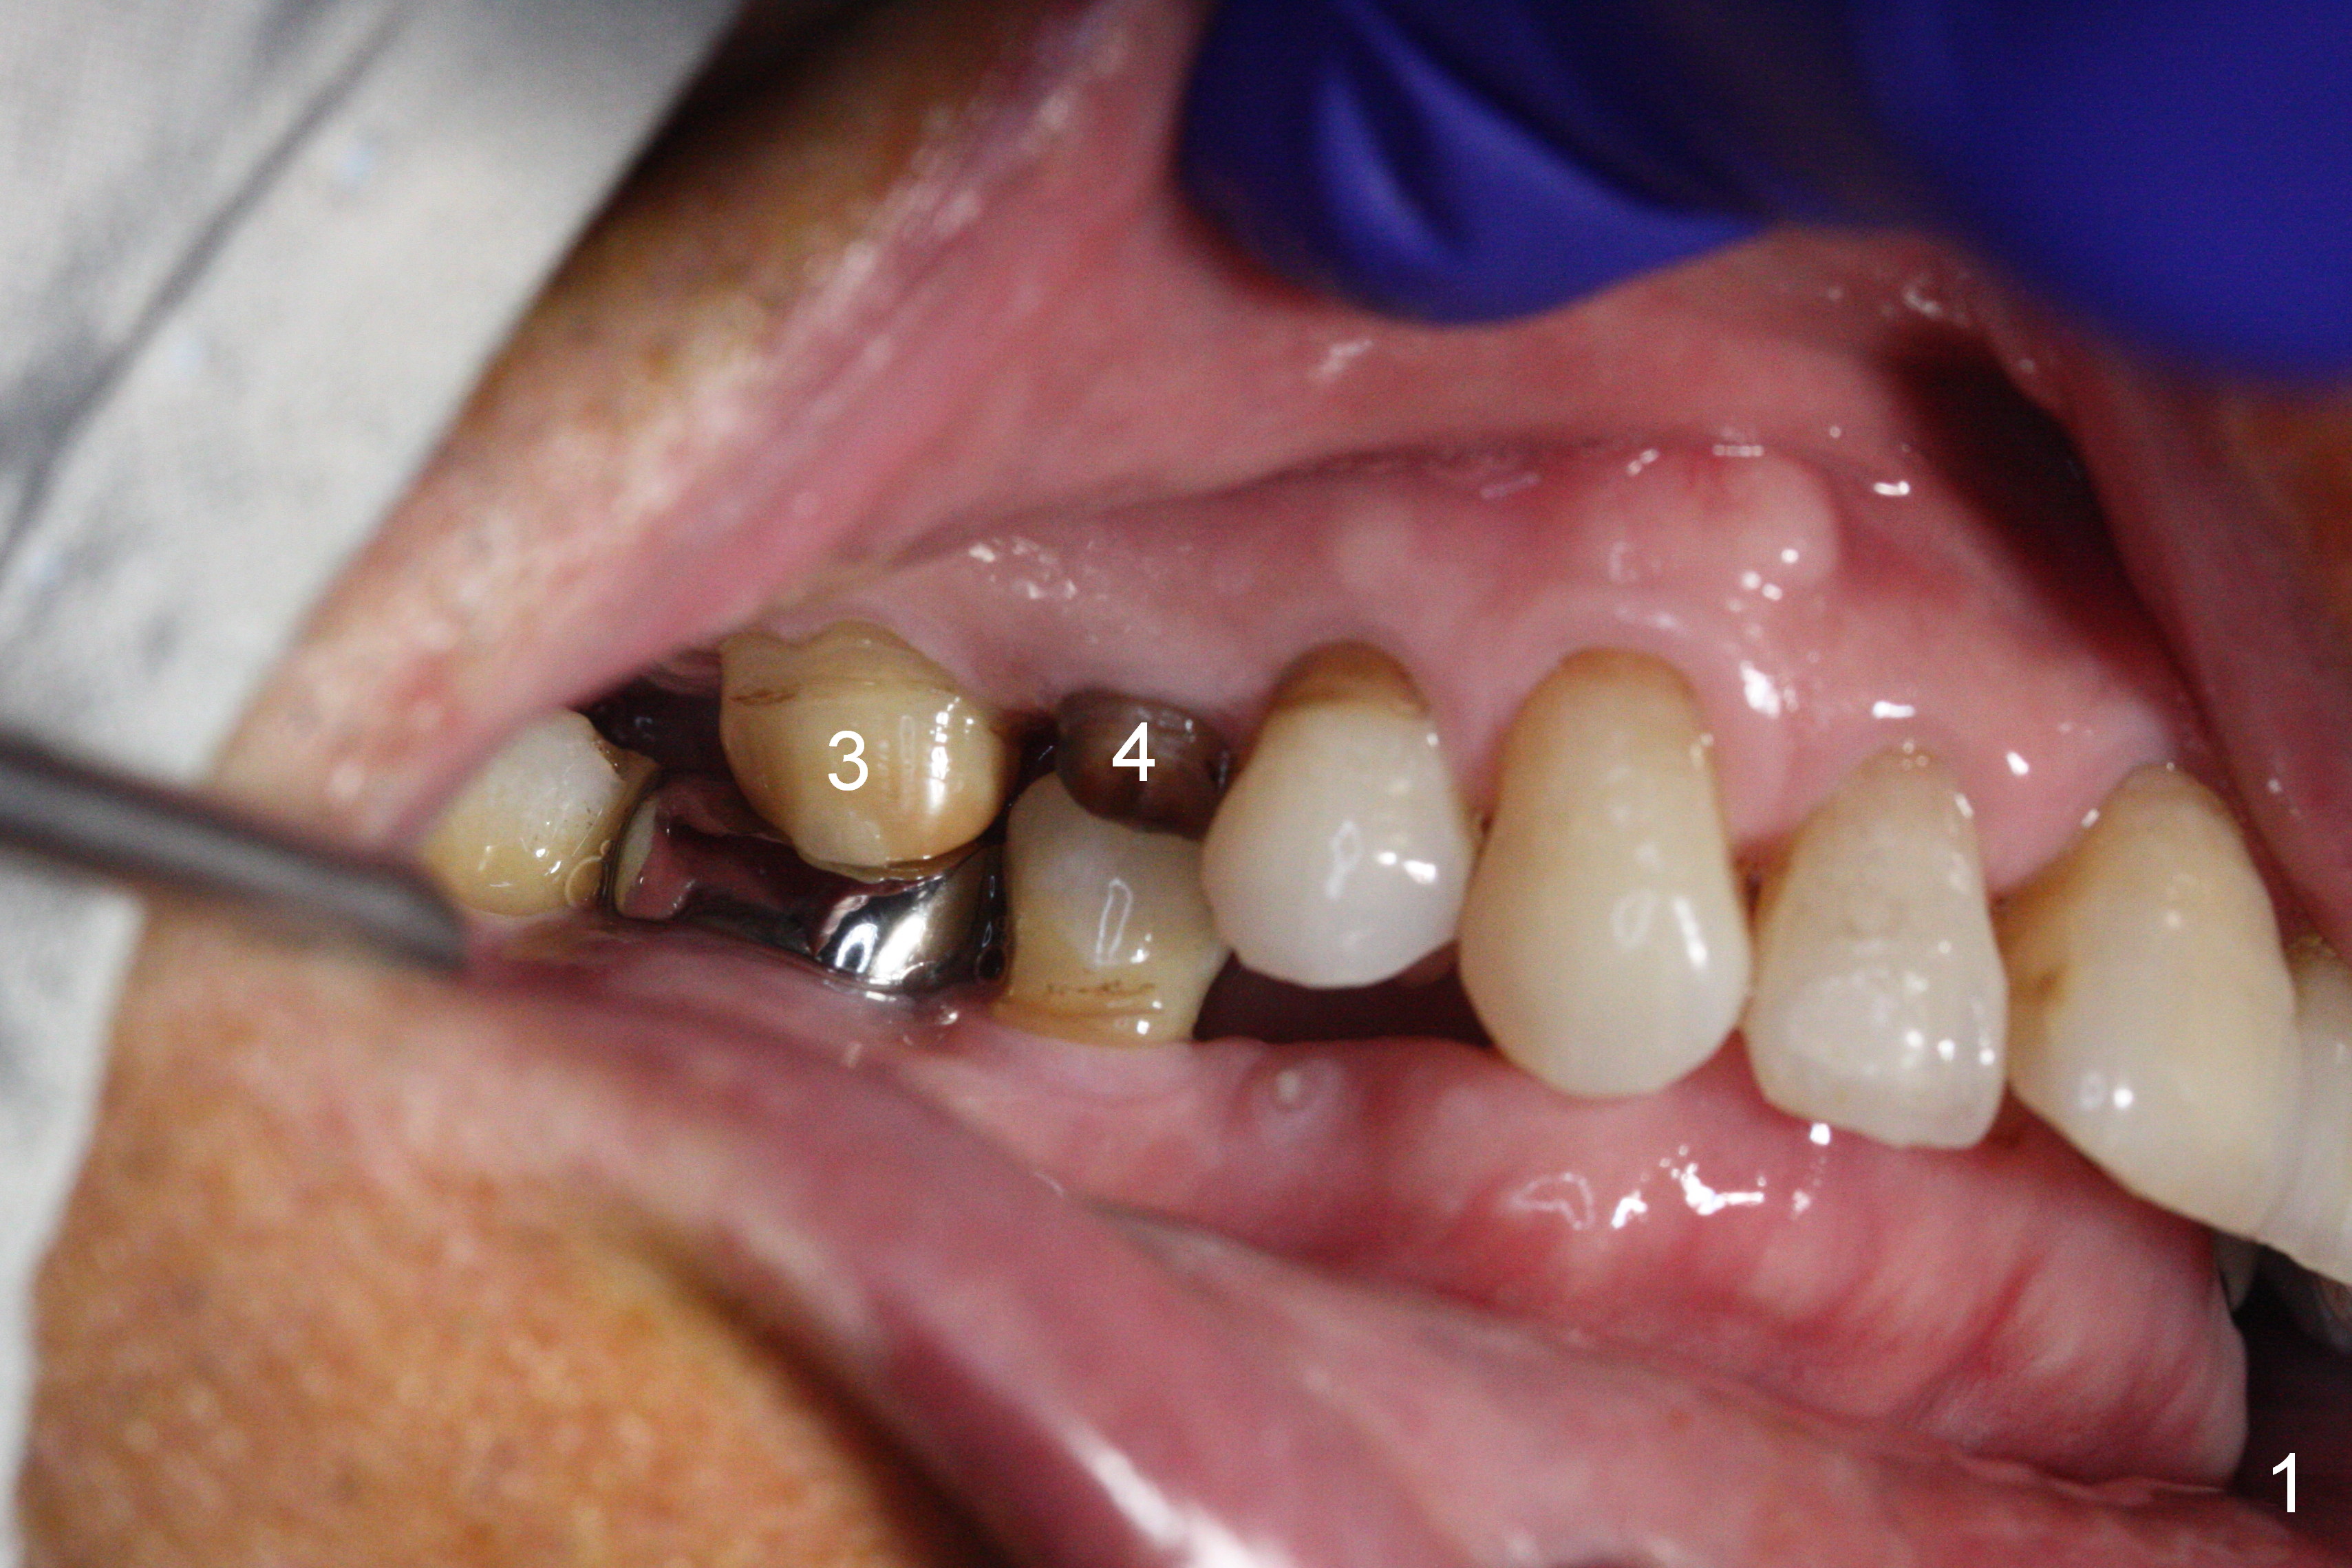

Preop exam shows posterior occlusal collapse (Fig.1) with #3 lost crown and #4 residual root. There is no ridge atrophy at #2 buccopalatally (Fig.2). The root stump of the tooth #4 is oblong, apparently consisting of 2 roots (Fig.3). There is a pointed septum at #4 socket (Fig.4, severe palatal wear of the anterior teeth (^)). After the septum is flattened with surgical handpiece and #8 round bur, 1.6 mm drill is used to start osteotomy in the septum, followed by Magic Drills (MD) and Magic Expanders (ME) alternatively. Osteotomy at #2 is initiated with Magic split, followed by MD and ME in the same manner. Dummy implants are tried in (Fig.5). Because of limited vertical height, Magicore (5.5x9(1) mm) is placed at #2, while a 4x13 mm FC implant 1-2 mm deeper than usual at #4 (Fig.6, ~ 55 Ncm). When a 5x4(2) mm pair abutment is placed at #4, there is no clearance between the Magicore at #2 and the abutment and the opposing dentition. A splinted provisional is fabricated at #3 and 4 to increase the posterior vertical height (Fig.7 P,8). In fact the occlusal contact is confined to the portion of the provisional at #3. The provisional has to extend to #4 to keep bone graft (Fig.6 *) and collagen plug in place. Liquid food is recommended at least 2-3 weeks, since there is no functional occlusal contact on the left. When the wound heals at #4 approximately 2-3 weeks, the splinted provisional can be sectioned with removal the portion at #4 to reduce micro-movement. By the evening the patient is doing well without nasal hemorrhage (sinus lift at #2 (Fig.6 *) or TMJ disturbance (due to increased vertical height).